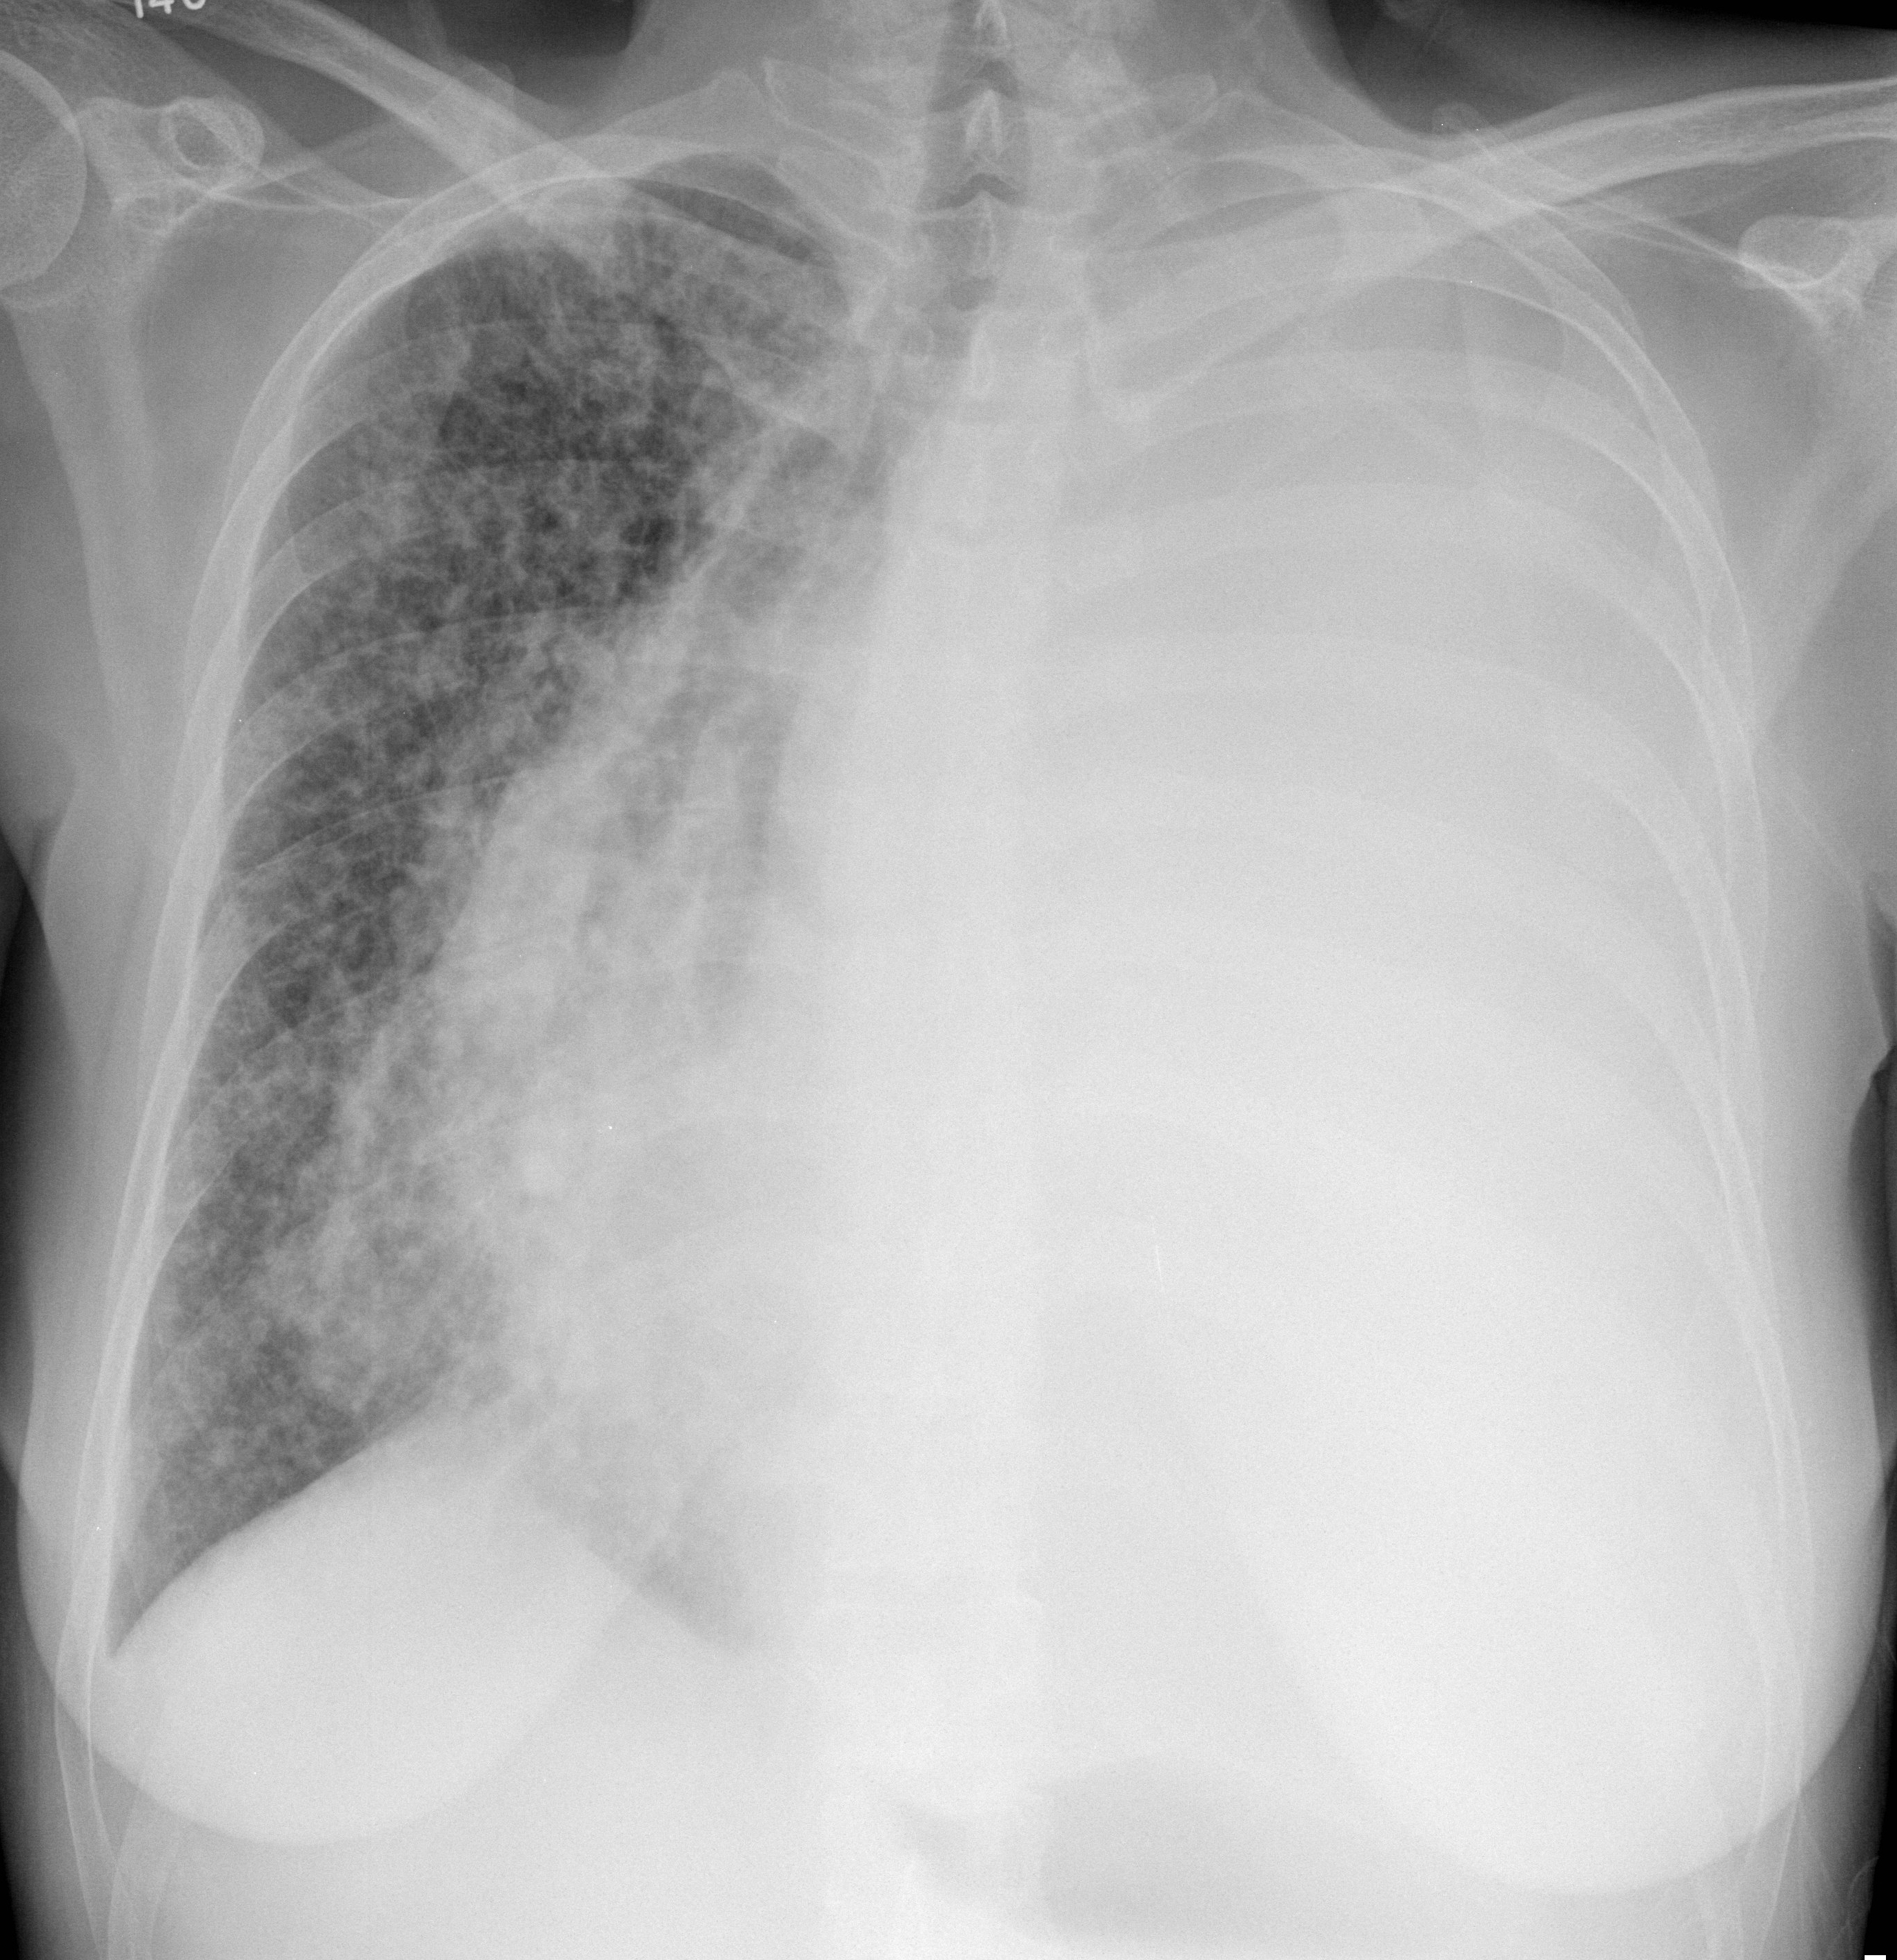

Gallery Lung Cancer Mets Mets and malignant ffusion

Mets and malignant ffusion